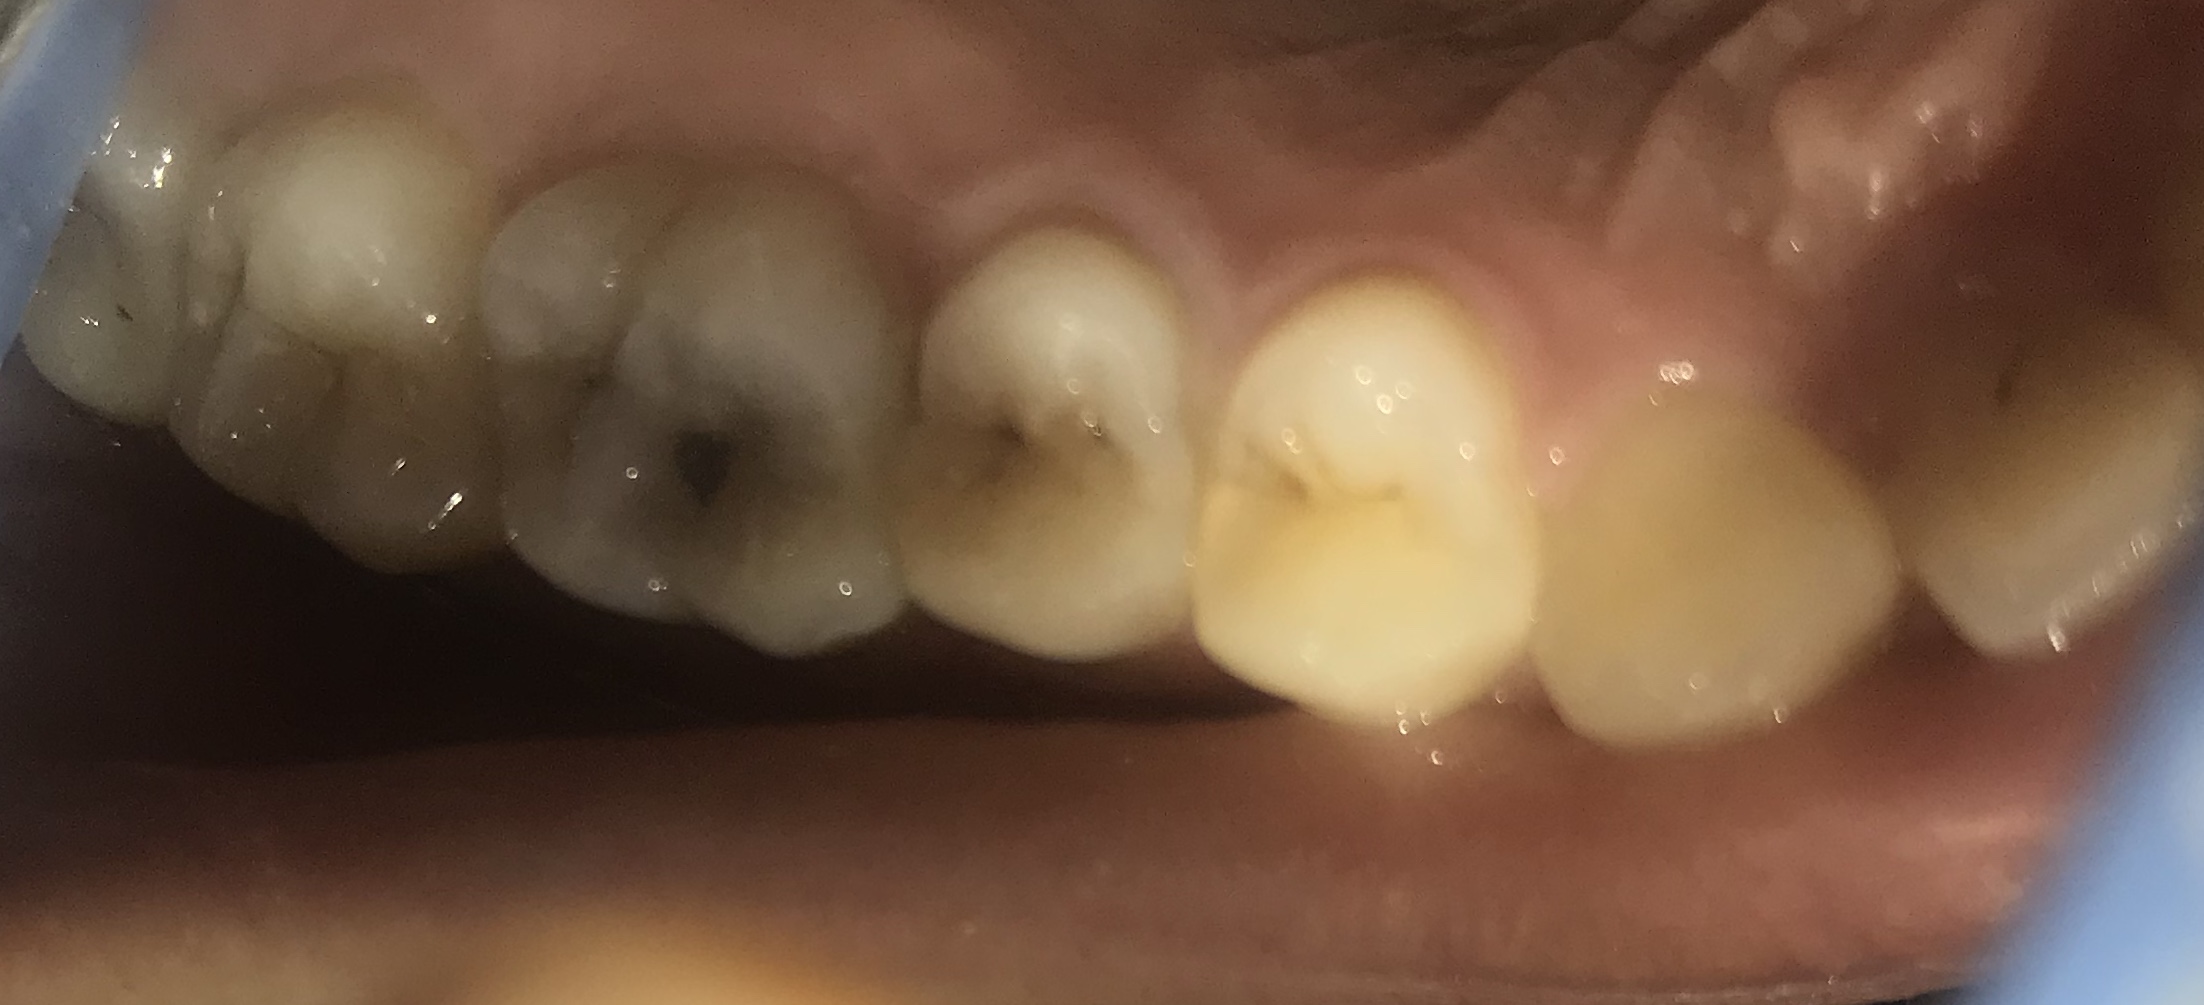

Aoa. I have extremely sensitive teeth I can’t Cold drink water. But nowaday there is a cavity in my molar that too sensitive to anything I eat or drink. I constantly have mild pain/sensitivity in my teeth. Also the teeth looks grey in colour. The x ray is attached below. What to do? The filling will do or RCT?

Hello. The X-ray is not very clear so no diagnosis can be made on the basis of X-ray. But judging by the looks of the cavity, filling might do. But again, no clear diagnosis as X-ray is not clear. For sensitivity, get scaling and poslisinh done. Also use sensodyne toothpaste.

Dear concerned with the picture it seems it will be saved with filling but x ray needs to be done again

without any delay get it done before its confirmed RCT case

x-ray is not clear you have to visit dentist for proper diagnosis and treatment no med will work until tha cause is removed so better get youself checked

Radiograph is not clear and you need a thorough examination

Dear pain is subsiding immediately after cold stimulus. Most probably tooth might only need filling.  But if pain stays for long root canal treatment  will be needed. X ray not very good quality  so can't  comment on it. I will advise to visit dentist earliest.